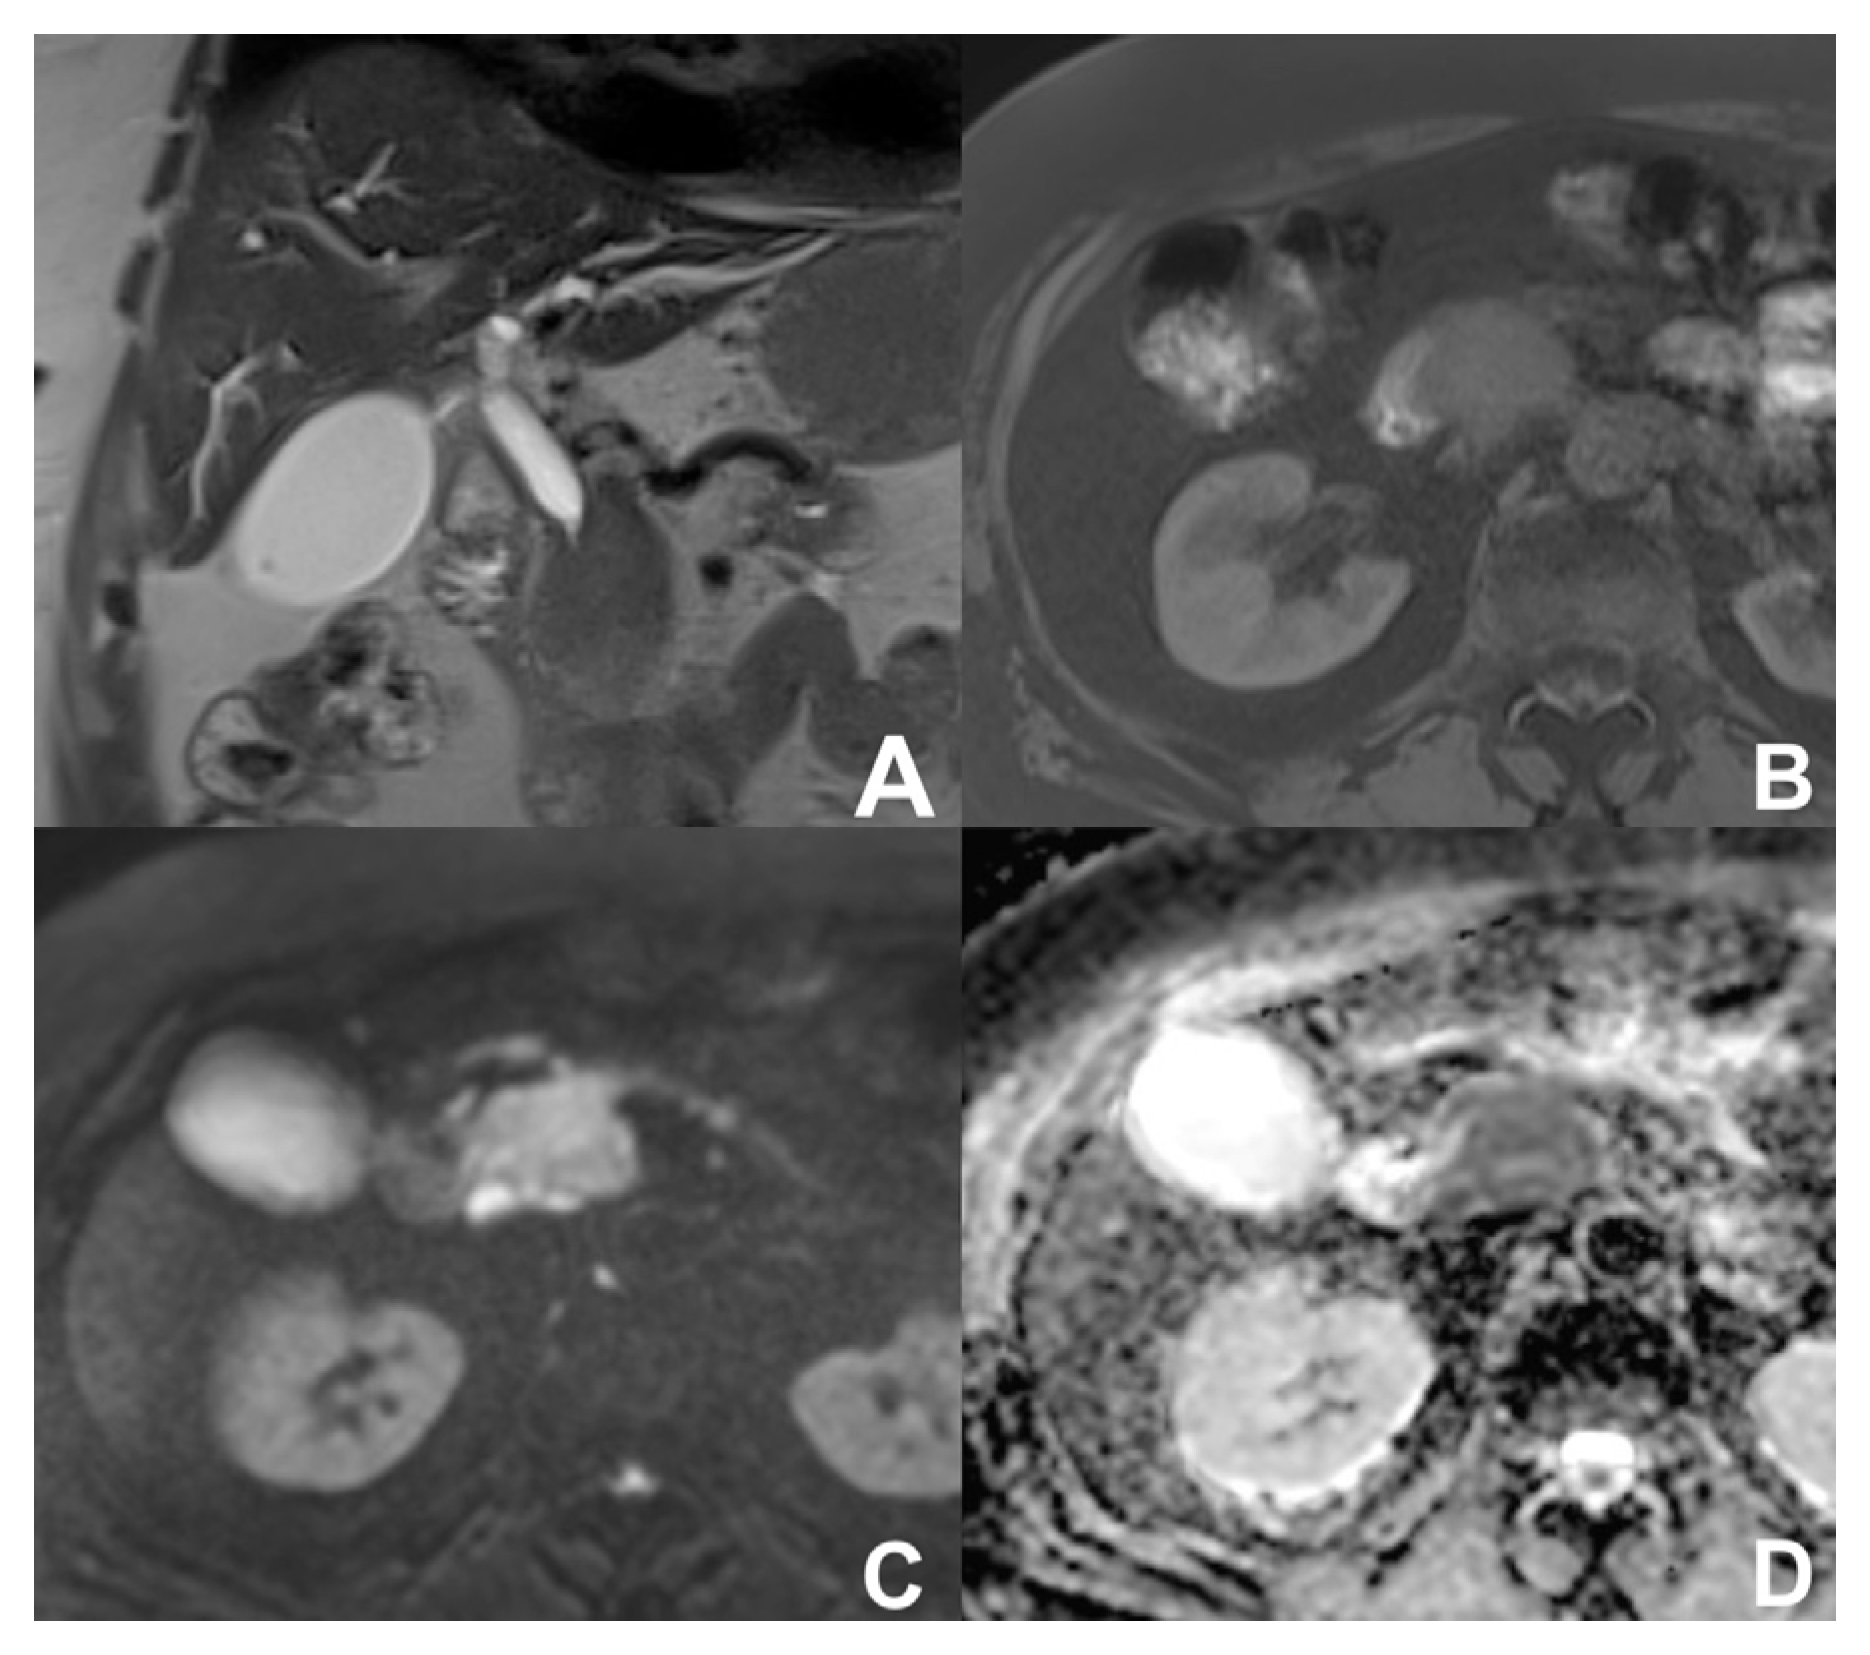

| Neuroendocrine tumor of the pancreas (PNEN) | HASTE T2 | AXIAL | -- | Anatomy and liquids analysis |

| Indications: MRI is useful for the detection of PNENs thanks to DWI and contrast enhancement. DWI can suggest the degree of differentiation of PNENs as high grade PNENS (G2-G3) usually show a marked restriction of DWI. Useful for the follow-up of small low-grade PNENs which cannot be resected. | HASTE T2 | CORONAL | -- | Anatomy and liquids analysis |

| GRE T1 FS | AXIAL | -- | pancreatic parenchima assessment | |

| DWI b 0–50–400–800 | AXIAL | -- | Restricted diffusion tipical of PNEN. Useful for multifocal PNENs | |

| GRE T1 3D DYNAMIC | AXIAL | Pre- 25″–70″–180″ | PNEN is most likely hypervascular | |

| MRCP 3D/2D | OBLIQUE CORONAL | Anatomy of wirsung duct | ||